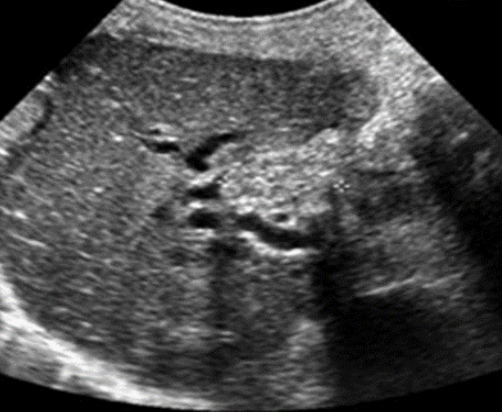

Acute Pancreatitis → sudden inflammation of pancreas from blockage of ducts and increased secretions

2D US: pancreas enlargement, hypoechoic parenchyma from edema, irregular ill-defined borders, peripancreatic free fluid, peripancreatic echogenic inflammatory fat, can have focal areas of inflammation/hypoechoic tissue